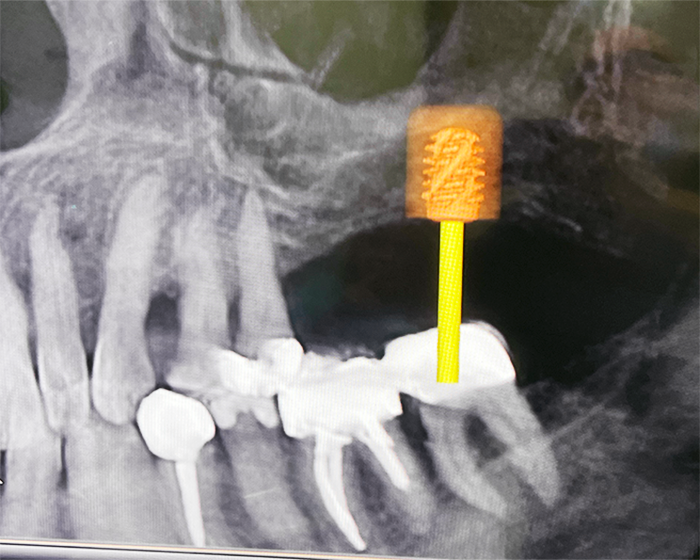

3-dimensionales Röntgen

DVT = Digitaler Volumen Tomograph

CBCT = „Cone Beam Computer-Tomography“

Auf dem Bild 1 und 2 kann man feststellen, dass die Wurzel in unmittelbarer Nähe des Unterkiefernervs (Nervus mandibularis) liegt und dass beim Operieren äusserste Vorsicht geboten ist.

Auf dem Bild 1 ist hinten am Weisheitszahn (8-er) eine Knochentasche sichtbar. Diese ist eine Folge vom Knochenabbau, welcher seinerseits eine Folge der Entzündung, welche wiederum ihrerseits durch Bakterien hervorgerufen worden ist. Diese haben sich unter die Schleimhauthäutchen eingenistet, welche oft den Weisheitszahn bedeckt.

Bild 2

Im Gegensatz zum 2-dimensionalem Röntgenbild kann man auf dem 3-dimensionalen DVT- Röntgen sehr gut unterscheiden, welche Wurzel bukkal (an der Wangenseite), lingual (an der Zungenseite) oder palatinal (auf der Gaumenseite) liegt und damit eine genaue Diagnose stellen.